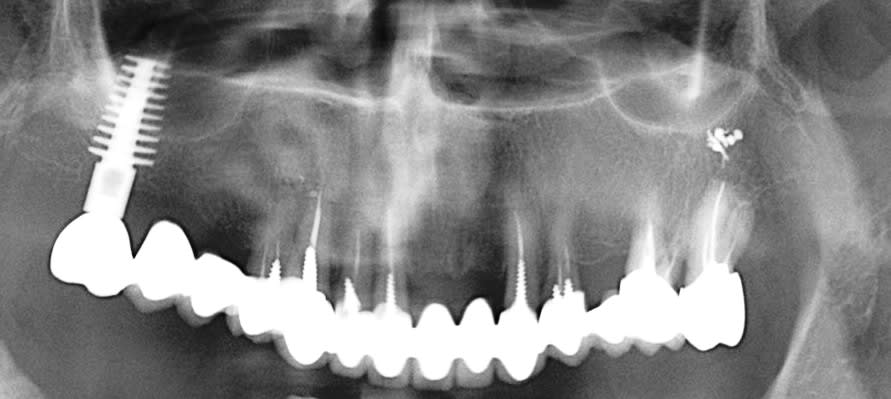

il est bien en 26 cet implant ou je me trompe?

et la 27 est bonne pour le bassinet, non?

çà va être un peu coton à gérer l'angulation de cet implant...celui qui a posé cet implant a du le faire avec la 7 taillée...je vois pas comment çà aurait pu passer autrement...(sauf si beaucoup de déformation due à la pano...)

27 a déjà jarté, j'aurais du faire la 28 dans le même temps mais elle ne me gêne pas pour l'instant.

Implant posé il y a... pfou, plus de 10 ans c'est certain, à l'époque il était solidaire de la 27.

Petite surprise à la dépose, j'y ai trouvé, entre la couronne scellée et le pilier transvissé, ce que j'ai imaginé être une chape en précieux. Surcoulée?

En antagoniste, c'est un banal stellite qui est prévu, le patient n'est pas pour l'instant emballé pour remettre le couvert en implanto, j'imaginais donc réaliser la 26 en unitaire, sans que cela ne m'emballe outre mesure.

Y'a-t-il des indications où les bridges dento implanto portés ont été validés? J'en ai vu quelques uns passer, sans que je puisse déterminer ce qui a conditionné leur réussite.

ton cas est intéressant et je ne vois pas en quoi l'implant te dérange, je crois qu'il doit mème être capable de supporter 26 et 26 (il n'y a pas 37)

Justement, c'est quoi la mécanique dans un cas comme celui-ci? Je me posais la question de solidariser 23 25 26. (et je rappelle pour info que les derniers cours dispensés en faculté sur les bridges dento implanto portés datent d'avant ma naissance)

23 est une planche pourrie, l'endo de la 14 pose question.

je n'ai pas vu le cas, donc simple hypothèse, l'équilibre mécanique, passe par une stabilité dans le temps, et avec un stellite en bas....pas simple.

mais je crois que l'implant peut supporter une extension sans soucis, (c'est déjà ce qu'il a non? je crois qu'il supporte 27.

Pour la 26, prenons les choses dans l'ordre:

Si je la réalise en unitaire, j'ai peur que l'orientation des vecteurs de force masticatoire finisse par impacter la connectique implantaire (qui a certes tenu jusque là)

Si je la solidarise à 23 25, c'est le différentiel de résilience qui va finir par... par quoi au fait? Périimplantite ou descellement partiel sur l'implant j'imagine.

J'avais donc 1 idée qui me venait, là comme ça: Quid d'un système d'inlay/contre-inlay non scellé entre 25 et 26? Ca a déjà été tenté?

(et oui la 23 sera conservée, malgré l'axe à babord toute: en l'occurence, une fois la céram déposée, j'ai pu constater que le tenon n'était là que pour justifier le SPR57 et que donc presque aucune force ne s'exerce sur le tenon. C'était la bonne surprise, sans ça j'avais prévu de déposer et repositionner un tenon fibré plus court et dans l'axe)

26 est costaud ... et pourrait servir dans un all on four...alors te prend pas le choux , si tu relie avec le bridge 23/25 ce n'est pas la peri-implantite le risque mais le bridge.

exemple d'un cas qui a plus de 25 ans pano contrôle 2008 et 2017 l'implant ne pose pas de problème